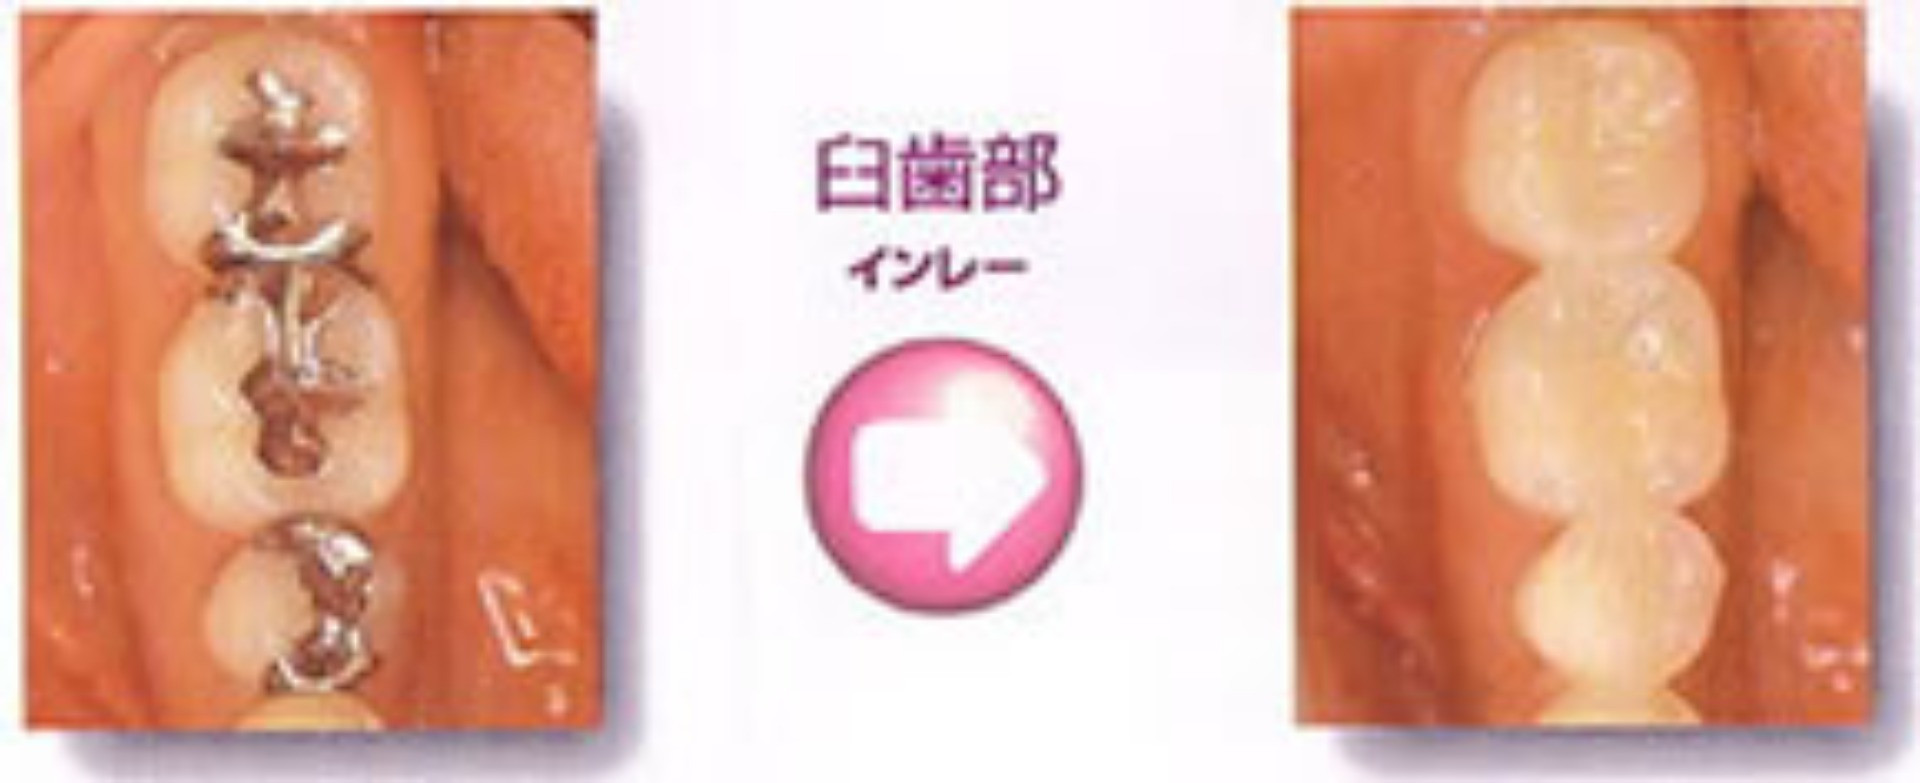

グラディアを使った治療例

| 奥歯にインレー(小さなつめ物)。 大きな口をあけると気になります。 |

グラディアでつくった修復物で治療。 自分の歯に合った色合いでとても自然になりました。 |

【治療前】 |

以前のむし歯治療で金属インレー(小さなつめ物)が入れてあります。 |

【金属の除去】 |

金属を外してきれいに清掃します。 |

【治療終了】 |

グラディアでつくった修復物を入れて治療終了。 色・形ともピッタリあっています。 まるで、元の自分の歯のようです。 |

歯と同様の色調で修復する美しい前歯は、もう当たり前の時代です。さらに見えにくい奥歯も白くきれいにしてみたいと思いませんか?

最新のハイブリッドセラミック修復材【グラディア】なら、奥歯も白く美しく治療できます。

歯とほぼ同じ硬さで、かみ合わせも自然です。